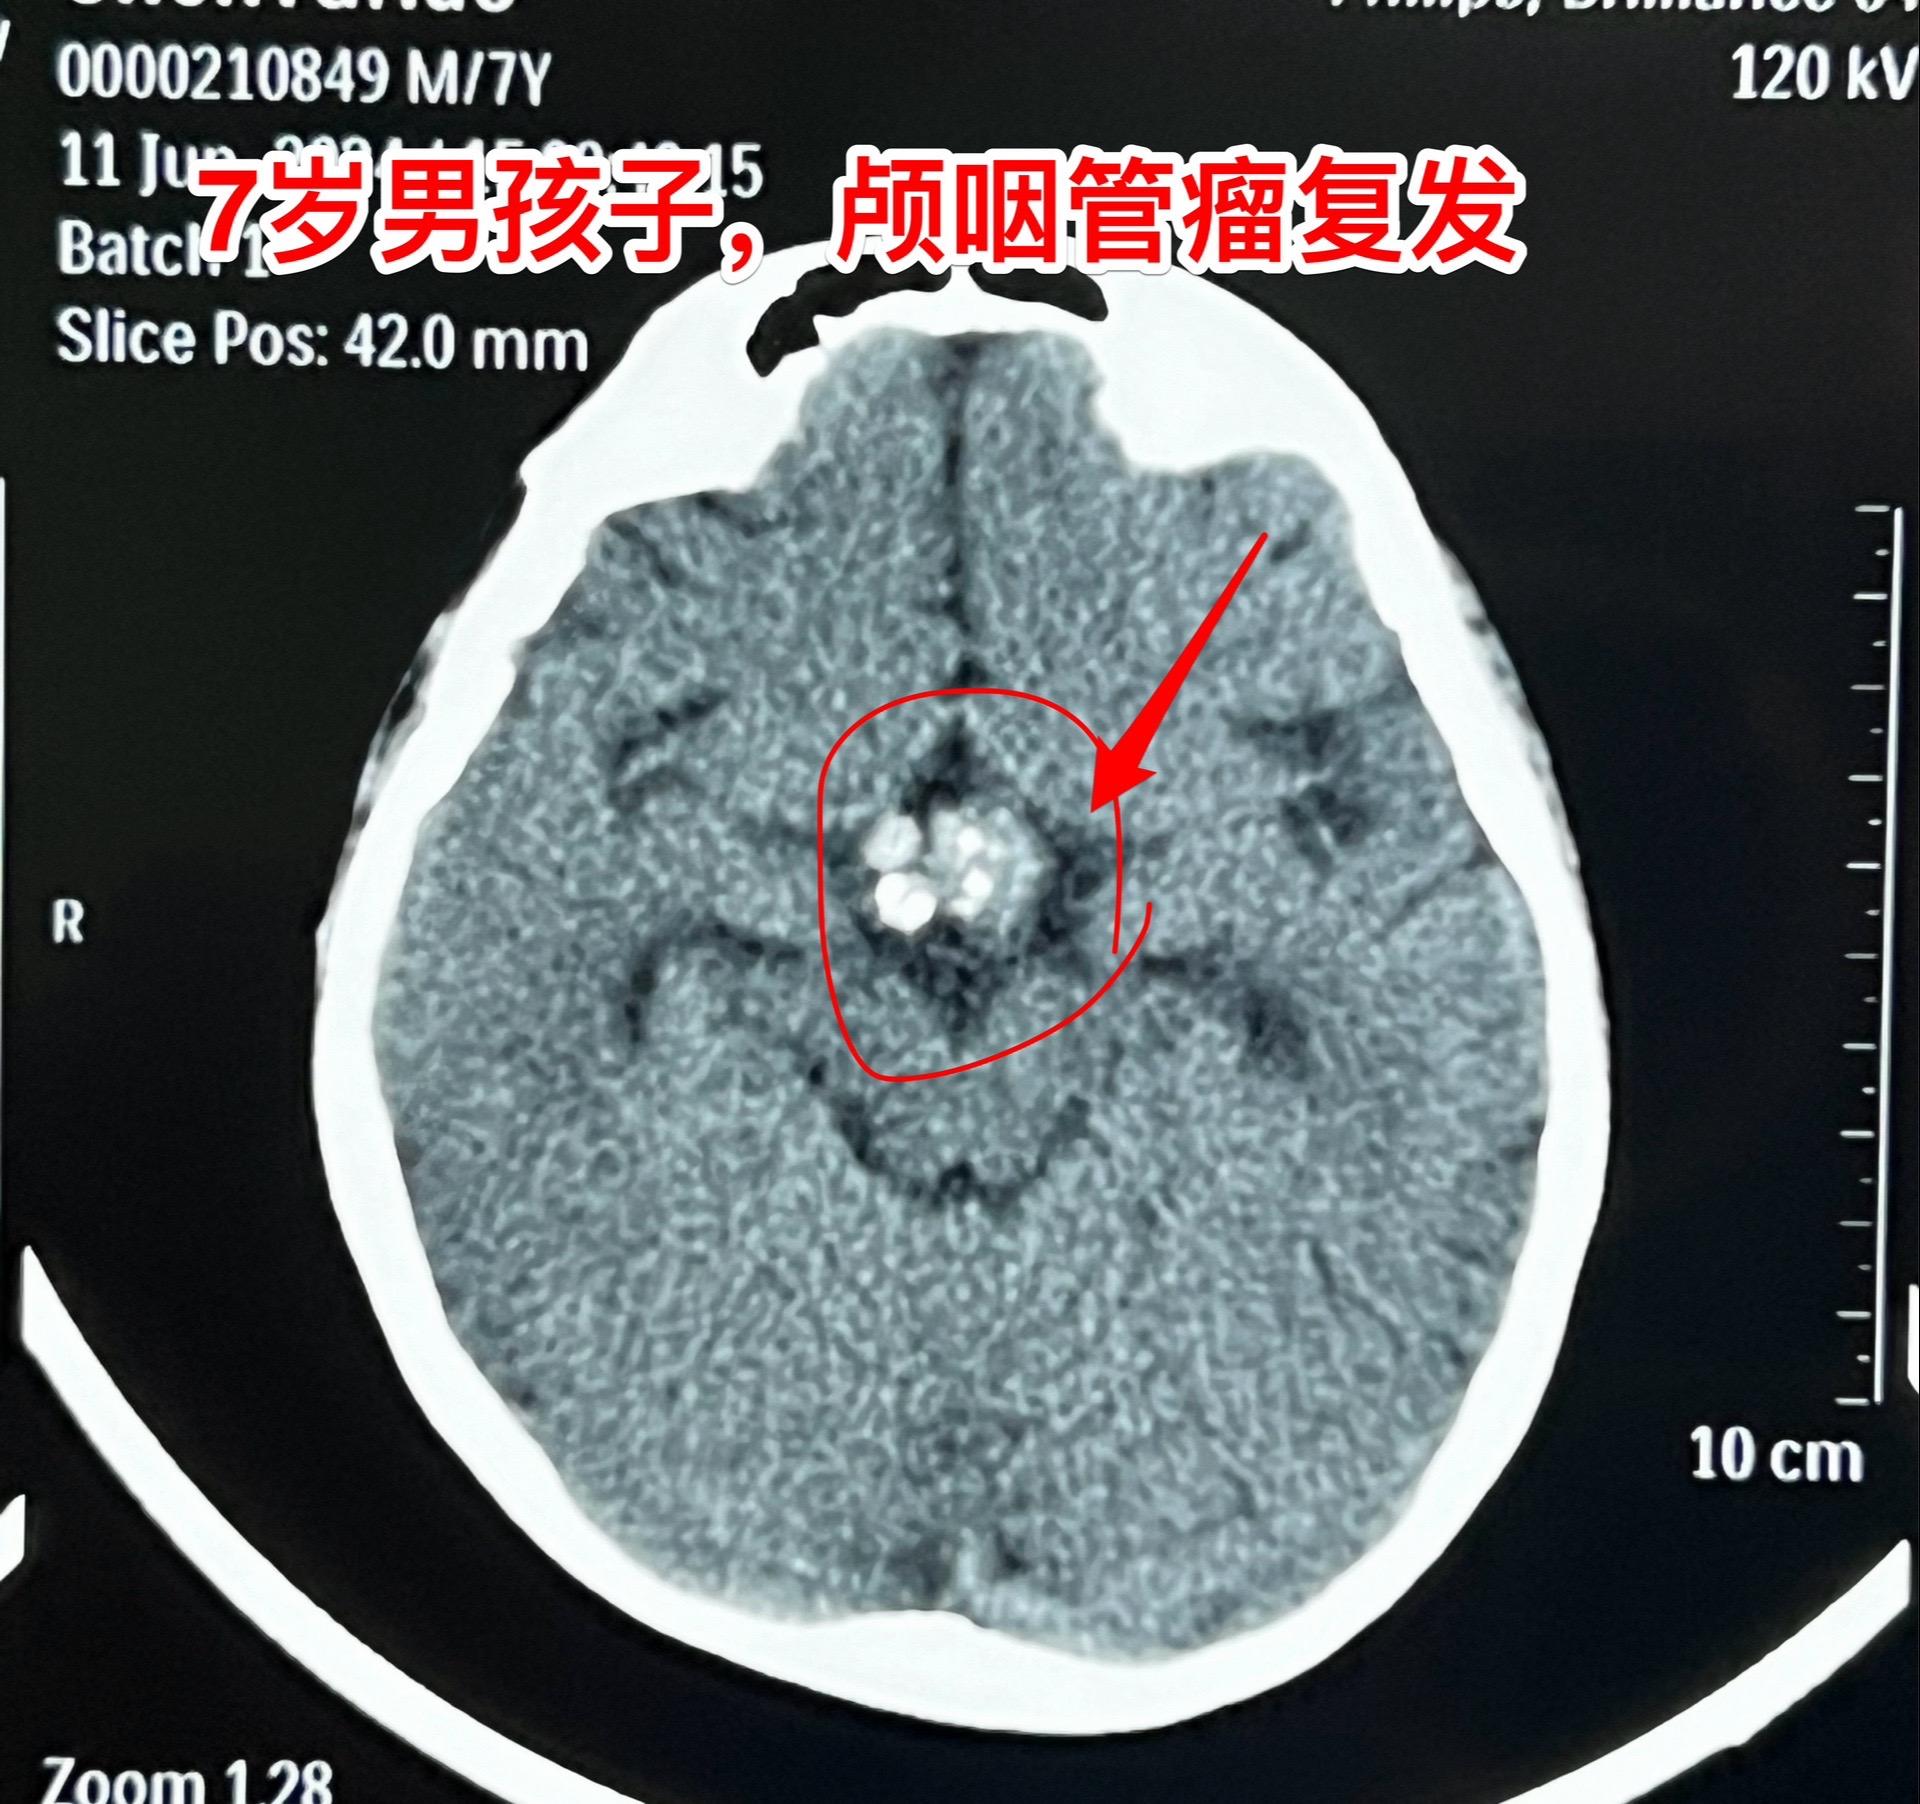

百日咳导致患儿颅咽管瘤手术推迟了三个月。7岁 男孩子三个月前因颅咽管瘤复发,住院准备作颅咽管瘤切除手术。 谁知意外事件不期而遇。 患儿咳嗽不止,只好出院到儿童医院治疗,经检测,咳嗽的原因是百日咳,经过治疗,咳嗽的问题彻底治愈了,过了三个月再次回到三博脑科医院。 2024年6月11日作了开颅手术。颅咽管瘤体积虽然不算大,其实不是一个肿瘤,而是四个肿瘤挨在一起了。 肿瘤当然是完全切除了。好事多磨!颅咽管瘤百日咳